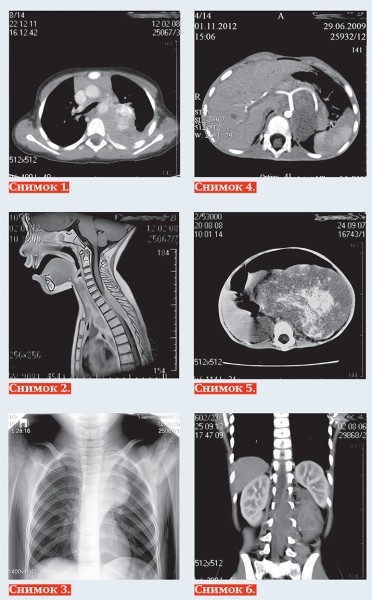

Тканевыми характеристиками нейробластомы являются: мягкотканная масса +25+35 HU на КТ (снимок 1), с гипоинтенсивным МР-сигналом на Т1-ВИ, изо/слабогиперинтенсивным сигналом на Т2, Т2 dark fluid — ВИ (снимок 2), негомогенная за счет кровоизлияний, очаговой кальцинации и некротических изменений, с умеренным контрастированием в паренхиматозную фазу, умеренной рестрикцией диффузии на МРТ.

Современная методика МРТ-диффузионного исследования всего тела нацелена на поиск метастазов опухоли. Радионуклидное исследование с I123-метайодбензилгуанидином (MIBG) выявляет и уточняет жизнеспособность опухоли с наибольшей чувствительностью (90 %) и специфичностью (до 100 %). Позитронно-эмиссионная томография с фтордезоксиглюкозой (ПЭТ-ФДГ) используется для дифференциальной диагностики нейроэндокринных опухолей.

Чаще всего нейробластома локализуется паравертебрально в реберно-позвоночной борозде по ходу симпатических ганглиев: в забрюшинном пространстве, надпочечниках, заднем средостении (снимок 3), полости таза, в области шеи. Генерализация опухоли с метастазированием в кости выявляется в 20 % случаев, в печень — 10 %, реже в легкие, головной мозг, подкожную клетчатку, при этом характерно поражение периорбитальных мягких тканей (1–5 %).

К наиболее важным визуально определяемым признакам опухоли (IDRF) относятся: поражение двух и более частей тела, вовлечение в опухоль более 50 % периметра артериального сосуда

(снимок 4), сдавление вены без визуализации ее просвета, инфильтрация прилежащего органа (снимок 5), компрессия трахеи и главных бронхов, инвазия сосудистых ножек почек, распространение в спинно-мозговой канал более трети просвета (снимок 6).